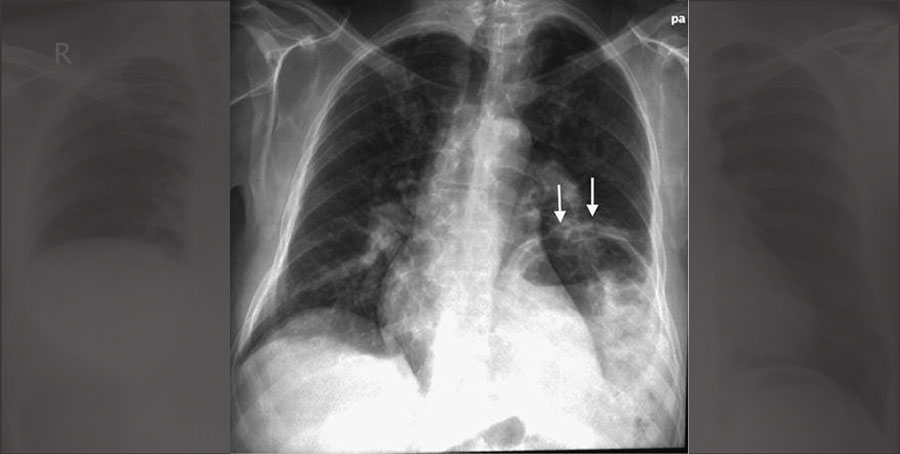

– هرزمان در عكس قفسه سينه، متوجه اختلاف سطحِ بيش از حد!! ديافراگمها شديد، هميشه همين ٢ تشخيص براتون مطرحه:

١. فلج عصب فرنيك

٢. اوانتراسيون ديافراگم

براى افتراق بين اين دو، به نكات زير توجه كنيد:

١. يادتون باشه اوانتراسيون ديافراگم در اكثر موارد، در سمت چپ رخ ميده! اين خيلى ميتونه كمكتون كنه!

مثلا اگه ديافراگم راست خيلى بالا رفته بود(مثل عكس پست قبل) بعيده كه اوانتراسيون باشه!

٢. اوانتراسيون ديافراگم، يه بيمارى مادرزاديه! پس معمولا در عكس قفسه سينه و يك نوزاد يا كودك نشون داده ميشه! (گرافيه پست قبل مربوط به يه فرد بالغ بود)

٣. خيلى مهمه كه بدونيد ، اوانتراسيون ديافراگم تقريبا بى علامته! اگه در صورت سوال ذكر شده بود كه بيمار تنگى نفس داره، ديگه بعيده كه اوانتراسيون باشه! (بيشتر بايد به فلج ديافراگم فكر كنيد)

٤. اينم خيلى مهمه كه، به ديافراگمى كه بالا رفته دقيق نگاه كنيد!

در اوانتراسيون، سطح ديافراگمى كه بالا رفته، هموار نيست و حالتِ كوهان مانند داره!مثل فلش هاى شكل زير!

اما در فلج ديافراگم، سطحِ كاملا صافى رو شاهد هستيم(مثل شكل پست قبل)

٥. ديدن نكاتى مثلِ تروما به قفسه سينه، توده در پارانشيم ريه و.. بيشتر ذهن رو به سمتِ فلج ديافراگم ميبره!

– پس گرافيه پست قبل مربوط به فلج ديافراگم بود!

– شكل زير هم گرافيه مربوط به اوانتراسيون (Eventration) ديافراگمه!